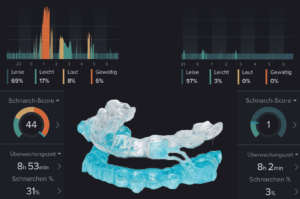

Schnarchschiene

Die von uns verwendete Silensor-sl® Schnarchschiene funktioniert nach dem Prinzip des Unterkiefervorschubs (Protrusion), wodurch eine Verengung im Rachenbereich erfolgreich verhindert wird und das Schnarchen effektiv vermindert bis komplett verhindert.

In der Grafik sehen Sie die eindrücklichen Aufzeichnungen einer Schnarch-App durch einen Patienten vor und nach Anwendung der Schnarchschiene.